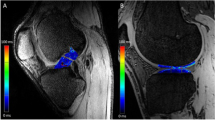

On MRI examination, the T1rho sequence was able to visualize tendinous portions of the AMB and PLB more clearly than the T2 map sequence in gray-scale images, and easily segregated the purely tendinous portion from surrounding synovial tissue (Fig. 1). Color-coded images were capable of visualizing the tendinous portion of the graft in both sequences. Mean T1rho values gradually decreased during the first year after ACL reconstruction (Fig. 2). Such trends were more prominent in AMB than in PLB. In contrast, reduction of T2 map values was dull in both AMB and PLB during the first year. When temporal changes were individually focused, T1rho values decreased more consistently among patients than T2 map values (Fig. 3).

The present study had two important findings. First, color coding images of both T1rho and T2 map sequences successfully visualized the purely tendinous portion of the ACL graft in the axial plane. T1rho and T2 map values of the tendinous portion gradually decreased in the first operative year. Second, both T1rho and T2 values at 1 year correlated well with anteroposterior knee laxity at 2 and 4 years, suggesting that both sequences could be used as surrogate measures of graft function during the postoperative course of ACL reconstruction. If increased graft signals can be assumed to indicate failed or delayed graft maturation in this study, clinical significance of graft signals can be seen for determining an appropriate timing to return to sport activities on an individual basis. Most surgeons to date have allowed patients to return to the original sport activities according to the time from surgery [25], isokinetic strength of muscles [26], one-leg hop test [27], and so on. No previous studies have used MRI findings as a measure for return to the sport due to a lack of reliability in the MRI assessment of ACL graft maturation.

Hypervascularity of the synovial membrane at 3–6 months may increase mean graft signals in the axial plane, which may obscure signals from the tendinous portion of the graft. This might be the case with the PDWI sequence, which has been perceived as a common sequence for not only cartilage, but also ACL. Although no significant differences were identified, T2 map values of PLB appear to increase from 3 to 6 months postoperatively and decrease thereafter, resembling the temporal pattern of conventional T2, PDWI, and gradient echo T2 sequences reported by previous studies [28, 30, 31]. This may suggest that PLB maturation was abrogated or that segregation of the purely tendinous portion from the surrounding synovium was difficult with the T2 map sequence. Ntoulia et al. assessed temporal changes in graft signals using Gd-DTPA and concluded that synovial tissue embracing the graft continued to display high intensity throughout the course of graft maturation, whereas the volume of synovial tissue peaked at 6 months and decreased until 12 months [9]. The peak graft intensity at 6 months documented in numerous past studies using conventional sequences may be attributable to an increased volume of synovial tissue. Jansson et al. proposed the same insight, that periligamentous tissue surrounding the graft largely contributed to increased graft intensity at 6 months postoperatively [32]. Detection of signals from the purely tendinous portion of the graft is important for proper assessment of graft maturation. In the present analysis with T1rho sequence, ROIs were easily set in the purely tendinous portion of AMB and PLB without color coding images, achieving substantial segregation from surrounding synovial tissue.